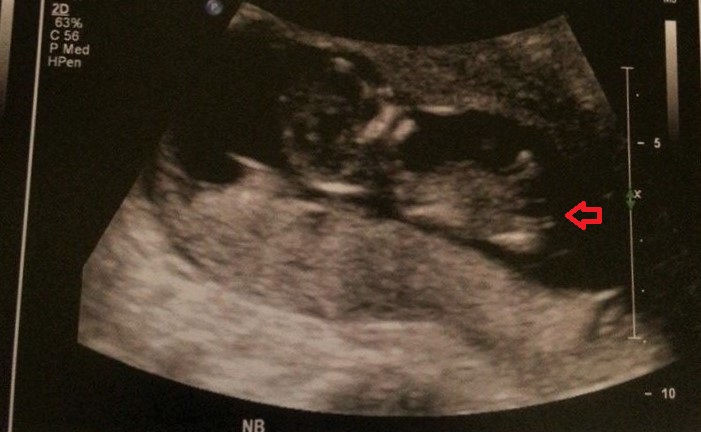

Above is what I *think* is a nub from my scan at 12+5... if so, any guesses on gender???

If that is the nub, my guess is girl

If that's nub I would lean blue due to the angle x

Leaning pink

blue

Not the greatest image, slight girl lean

Pink for sure!!